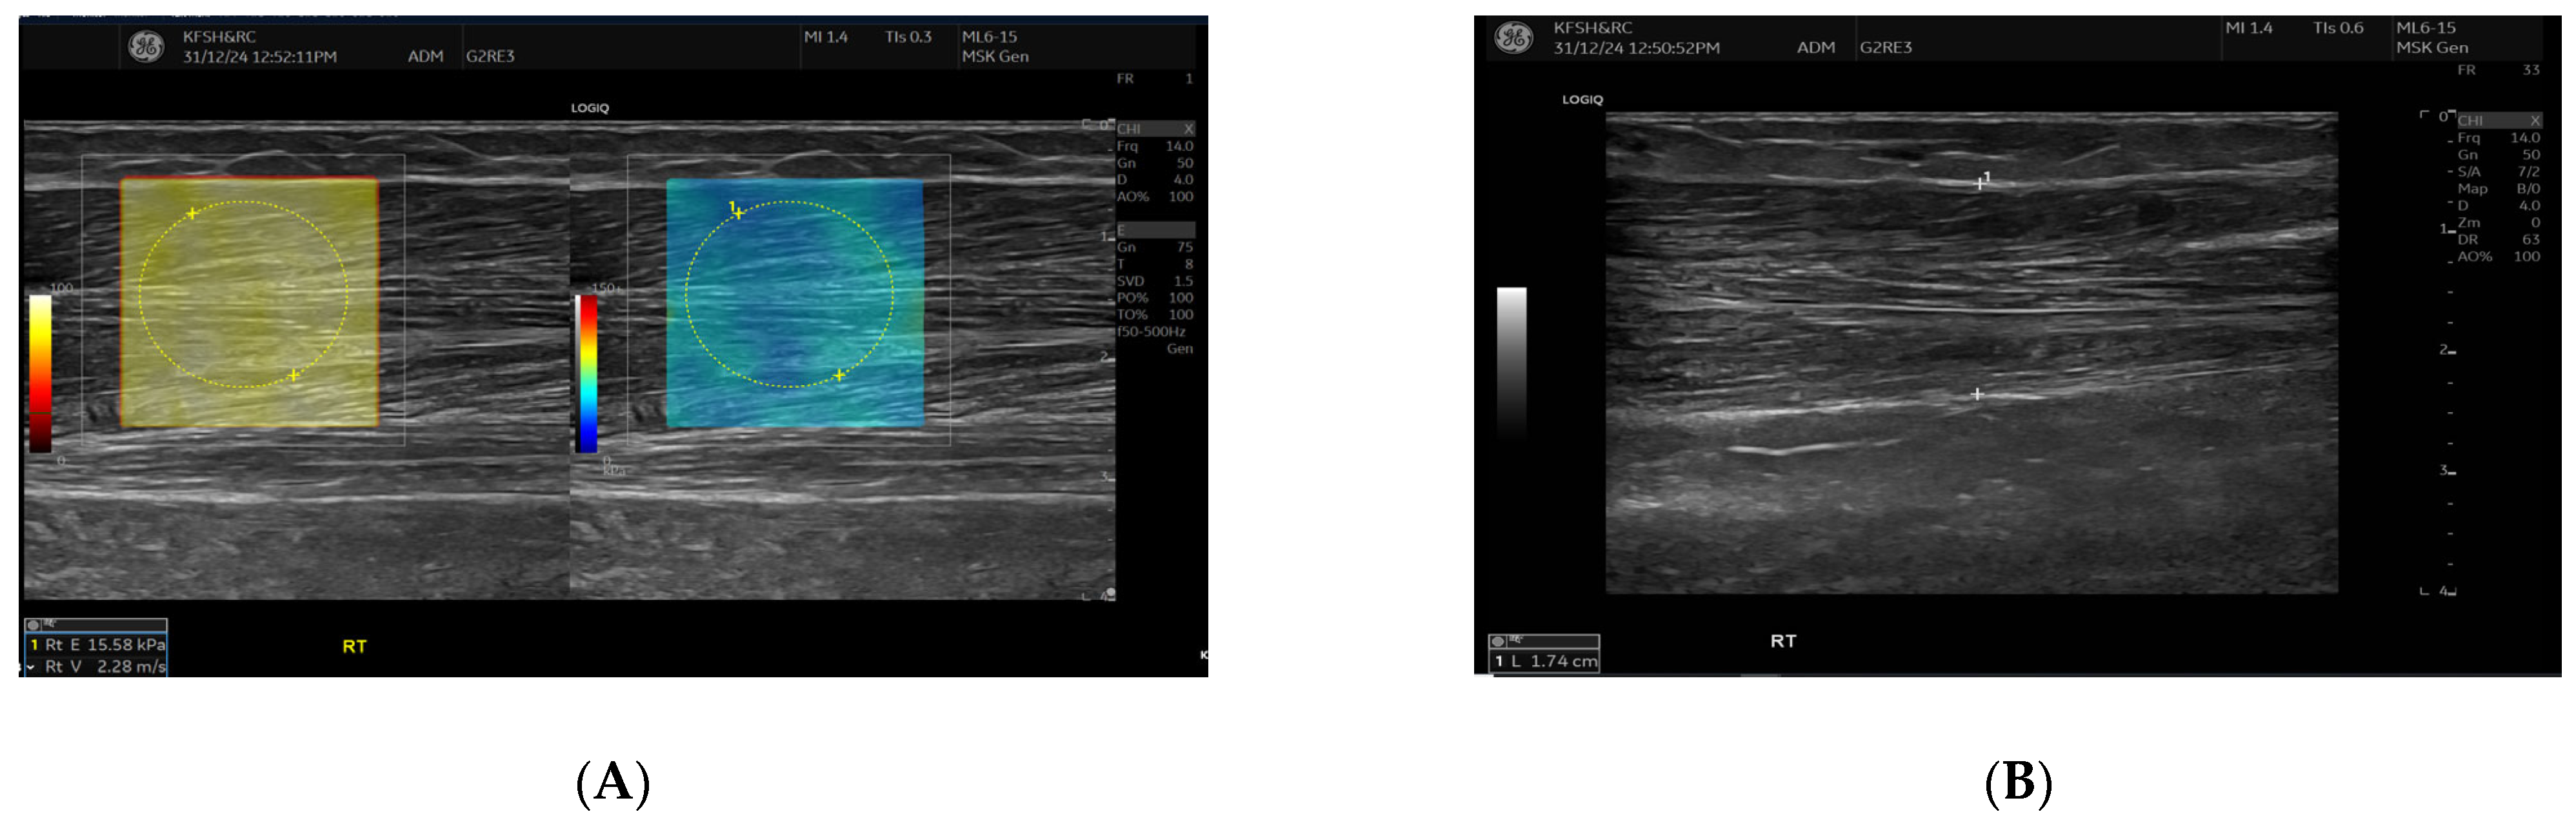

Figure 3.

This figure shows the comparison of brachioradialis muscle stiffness between the fistula and the contralateral arm. Shear wave elastography images showing stiffness measurements of the brachioradialis muscle. The left panel (fistula side) demonstrates a mean elasticity (velocity 2.13 m/s), while the contralateral arm (right panel) shows slightly higher stiffness (velocity 2.28 m/s). Measurements were taken in the mid-muscle belly using a high-frequency linear transducer, with Colour maps indicating relative stiffness (warmer colours represent higher stiffness).